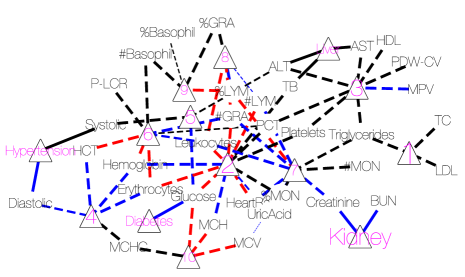

Conditional on , the posterior estimates of the PD and SD models are shown as a heatmap in Figure 7 with green, black and red cells representing 1, 0 and -1, respectively. The nature of the figure as a single heatmap with two blocks, for PD and SD, respectively, highlights again the nature of the model as a “double” feature allocation with matching subsets of patients and symptoms. The model allocates both, patients and symptoms, to latent diseases. As mentioned before, DFA can also be interpreted as an edge-labeled network. We show the same results as in the heatmap as a bipartite graph in Figure 8(a). The full inferred model would be a tripartite network, as in the bottom portion of Figure 4. However, we omit the patient nodes in Figure 8(a) , lest the figure would be overwhelmed by the patient nodes. Instead, we summarize the patient-disease relationships by specifying the font size of the disease node (triangle, purple font) proportional to the number of linked patients. Latent diseases are labeled by numbers and a priori known diseases are labeled by name. Symptoms are shown in black font, with lines showing the links to diseases. Dashed lines are symptom-disease relationships that are inferred from the data whereas solid lines are fixed by prior knowledge. Black lines indicate that symptoms are binary. Red (blue) lines indicate suppression (enhancement) relative to the normal range. Line widths are proportional to the posterior probabilities of edge inclusion.

We find 239 patients with impaired kidney function or kidney disease, 183 patients with hypertension and 93 patients with liver disease. The prevalence of kidney disease is slightly higher than the national average 16.9% (Zhang et al. , , 2012) probably because of the elderly patient population in this study. We caution that the estimated prevalence from our analysis should be viewed as an estimate for the lower bound of the actual prevalence in the target patient population because we are not explicitly addressing confounders such as treatment. For example, our estimated hypertension prevalence (18.3%) is much lower than the national average 57.3% (Zhang et al. , , 2017), probably simply due to successful and widely available treatment. Individuals who were previously diagnosed with hypertension and comply with the prescribed medication may not show any symptom (high blood pressure) in the physical examination.

We identify additional 10 latent diseases with prevalence of 493, 218, 192, 174, 114, 82, 64, 24, 15, and 15 patients. Some of the latent diseases are quite interesting. Latent disease 1 is lipid disorder, associated with high total cholesterol (TC), triglycerides and low density lipoprotein (LDL). Cholesterol is an organic molecule carried by lipoproteins. LDL is one type of such lipoproteins, commonly referred to as “bad” cholesterol. At normal levels, TC and LDL are essential substances for the body. However, high levels of TC and LDL put patients at increased risk for developing heart disease and stroke. Triglycerides are a type of fat found in the blood which are produced by the body from excessive carbohydrates and fats. Like cholesterol, triglycerides are essential to life at normal levels. However, a high level is associated with an increased chance for heart disease.

Latent disease 3 can be characterized as thrombocytopenia-like disease which causes low count of platelets, decreased plateletcrit (PCT) and coefficient of variation of platelet distribution (PDW-CV), and increased mean platelet volume (MPV). Patients with low platelets may not be able to stop bleeding after injury. In more serious cases, patients may bleed internally which is a life-threatening condition.

Latent disease 4 is a polycythemia-like disease, associated with elevated mean corpuscular hemoglobin concentration (MCHC), hemoglobin, erythrocytes and hematocrit (HCT). These symptoms match exactly the symptoms of polycythemia, a disease that gives rise to an increased level of circulating red blood cells in the bloodstream. Polycythemia can be caused intrinsically by abnormalities in red blood cell production or by external factors such as chronic heart diseases.

Interestingly, like latent disease 4, latent disease 6 is also related to hemoglobin, erythrocytes and HCT. However, it is linked with a decrease in these levels; hence we refer to the disease as anemia.

Latent disease 7 suggests bacterial infection with increased leukocytes, granulocytes (GRA) and heart rate, and decreased monocytes (MON) and lymphocytes (LYM). The immune system, specifically the bone marrow, produces more GRA and leukocytes to fight a bacterial infection. As a result, the relative abundance of MON and LYM decreases.

Relatedly, latent disease 8 may be caused by viral infection. Viruses can disrupt the function of bone marrow which leads to low levels of leukocytes and GRA, and high levels of LYM.

Latent disease 9 is related to allergy with abnormal basophil, GRA and LYM.

Latent disease 10 suggests that a small group of patients may have malnutrition, which is linked with low blood glucose and anemia-like symptoms such as low corpuscular volume (MCV) and corpuscular hemoglobin (MCH).

We remark that although there are clear interpretations for most latent diseases found by DFA, latent diseases 2 and 5 cannot easily be interpreted as specific diseases. Latent disease 2 is associated with 12 symptoms, which is likely beyond the number of symptoms of any single disease. Most of the symptoms, such as platelets, leukocytes and lymphocytes, are due to a weak immune system. Considering the elderly population of this dataset, aging could be a reasonable cause. Decreased heart rate and low glucose level can also be explained by aging. Latent disease 5 is linked with elevated systolic blood pressure and glucose. While those two symptoms may not be simultaneously linked to the same disease, their co-appearance should not be too surprising because the co-existence of hypertension and diabetes (to which blood pressure and glucose are known to be linked) is quite common (De Boer et al. , , 2017).

As a comparison with results under alternative approaches, we consider inference under SLFM, applied directly to the blood test results, without converting to binary or ternary symptoms. The tuning parameter was set to 1 to approximately match the number of latent diseases found by DFA. SLFM implements inference on sparse symptom-disease relationships as shown in Figure 8(b). Although there is no known truth for symptom-disease relationships, it is difficult to interpret certain links. While uric acid may play some role in certain diseases, we do not expect it to be related to 5 out of 12 latent diseases. In addition, both latent diseases 5 and 6 are related to platelets only, which should be collapsed into one disease. We also ran LSFM with larger but found similar results. For example, when , SLFM identifies 20 latent diseases, 17 of which are associated with uric acid. These somewhat surprising results may be due to the assumption of normality and linearity of SLFM, and taking no advantage of prior information.

As already briefly commented in Section 1, graphical models may be also employed for finding hidden structures of the symptoms. We run a birth-death MCMC algorithm (available in the R package BDgraph, Mohammadi & Wit, 2015) for 50,000 iterations to learn a Bayesian graphical model. A point estimate is shown in Figure 8(d). Symptoms that form cliques of size greater than 3 are marked by circles. Some of the findings are consistent with those by the DFA. As an illustration, the clique of TC, triglycerides, LDL and HDL is very similar to latent disease 1 in Figure 8(a). However, although graphical models can find latent patterns that are not immediately obvious in the correlation structure (Figure 1a), like SLFM, it lacks inference on patient-disease relationships. Moreover, identifying cliques or other graph summaries as disease is an arbitrary choice.

As demonstrated in Section 6, inference under the DFA model includes inference on patient-disease relationships. Neither of the alternative approaches, SLFM or graphical models, include this capability. Knowing patient-disease relationships is crucial in prioritizing limited medical resources. The proposed inference for the DFA is fully Bayesian. Therefore, it outputs not only point estimates but also the associated uncertainties through, e.g., the posterior probability of symptom-disease relationships (reflected by the line width in Figure 8(a)). SLFM is implemented using an Expectation-Maximization (EM) algorithm. It can quickly get point estimates, but does not include uncertainties.